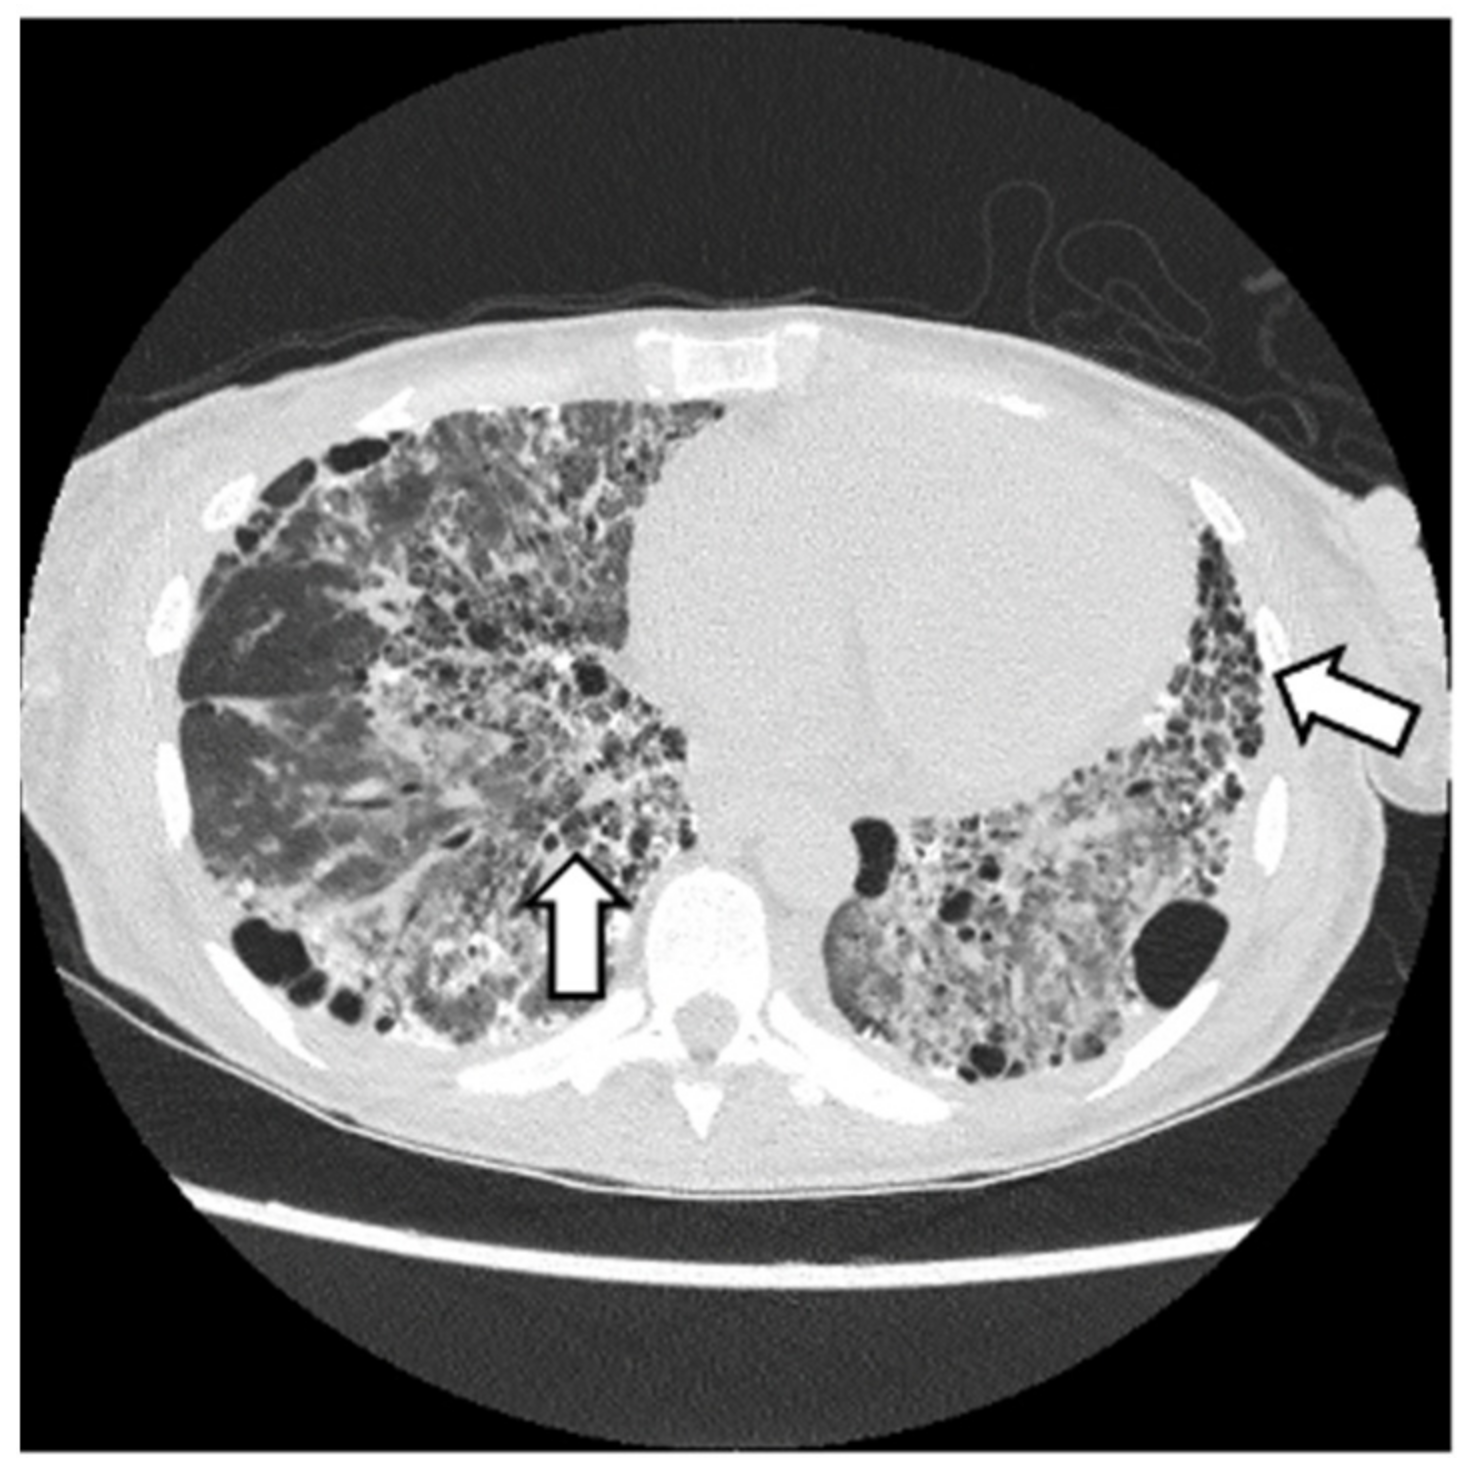

2.3. Case Report 3

6.2. Histopathologic and Radiographic Findings in Myositis-Associated ILD